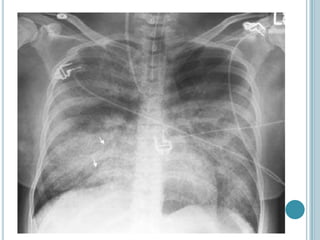

 Estudios de imagen

Es típico que la radiografía de tórax demuestre un

proceso de ocupación alveolar difuso y simétrico.

Cuando se realiza tomografía computada, la

distribución de los espacios ocupados suele observarse

menos homogénea

DIAGNOSTICO EDEMA PULMONAR NOCARDIOGENICO:  Clínica: suele existir menor actividad simpática y, cuando existe cianosis, es causada por hipoxemia arterial. La piel puede estar caliente en lugar de fría, húmeda y pálida.  Estudios de imagen Es típico que la radiografía de tórax demuestre un proceso de ocupación alveolar difuso y simétrico. Cuando se realiza tomografía computada, la distribución de los espacios ocupados suele observarse menos homogénea